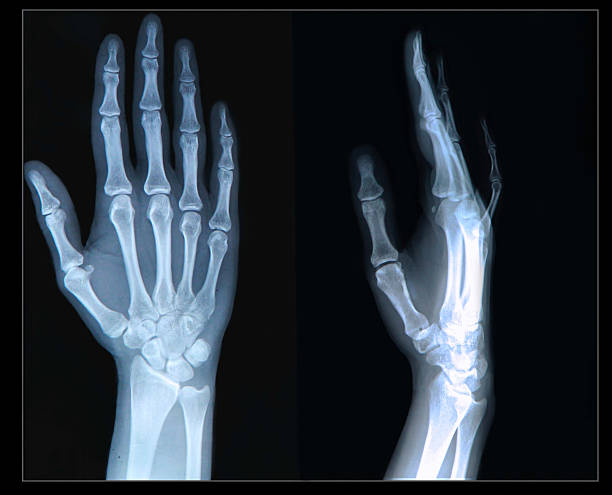

또한, 골수염 진단을 위해서는 엑스레이, MRI, CT 스캔, 뼈 스캔 또는 초음파와 같은 영상 검사를 실시할 수 있는데, 이는 뼈 손상의 정도를 나타낼 수 있습니다.